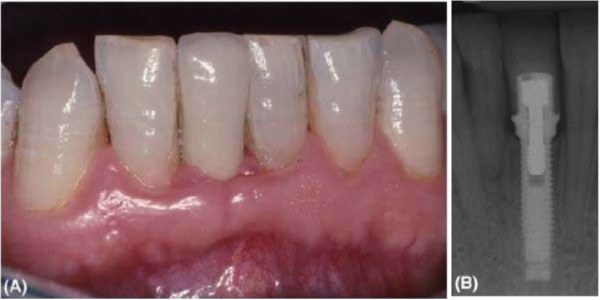

(A) Răng cửa bên hàm trên được thay thế bởi một implant cho thấy hình dạng mô mềm tốt và thẩm mỹ. (B) Hình ảnh X quang của implant, trường hợp này đường kính nhỏ khoảng 3.3 mm Nobel Biocare. Implant đường kính nhỏ thích hợp cho vị trí chịu lực ít.